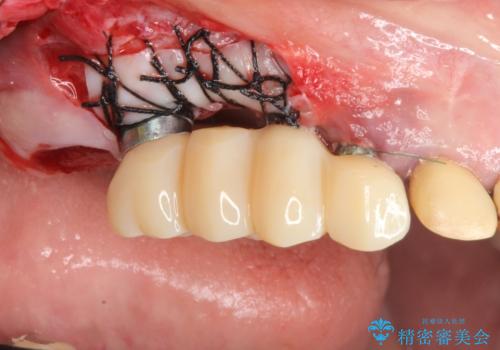

既に埋入されているインプラントは位置が悪いのでそのまま骨内に留置することとし、新たに咬合機能を回復すべく3本のインプラントを埋入すると同時に吸収した骨幅を増やし、安定してインプラントで噛める環境整備を目指します。

- 120万円(インプラント×3 チタンカスタムアバットメント×3 メタルボンドクラウン×3 骨造成 歯肉移植)費用は治療当時の料金となります

インプラントが長持ちするために、インプラント周囲の十分な骨量・角化歯肉の存在・安定した咬合を一つづつ整備する治療を行いました。